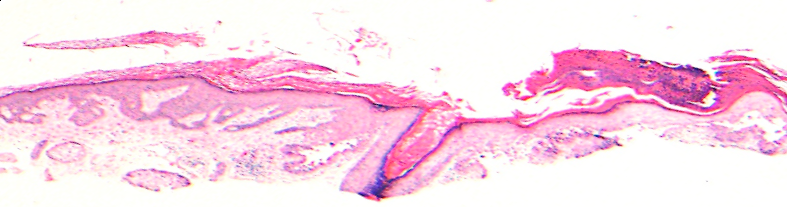

VA183: Right Cheek, Adjacent, Normal